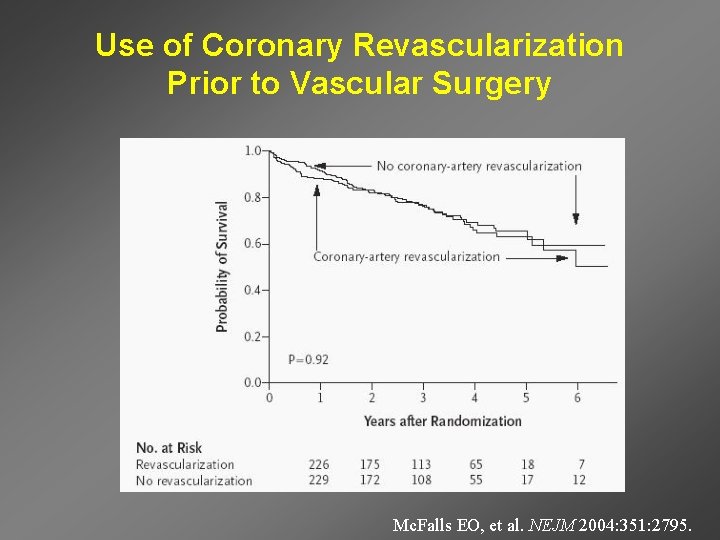

Use of Coronary Revascularization Prior to Vascular Surgery Mc. Falls EO, et al. NEJM 2004: 351: 2795.